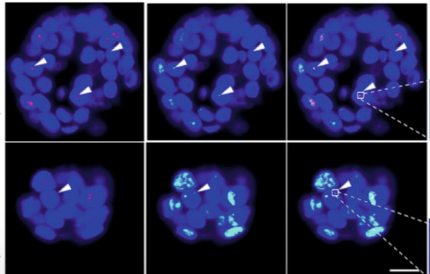

Scoprire le vie che controllano l'immortalizzazione utilizzando organoidi tumorali

Il partner di p-care Stefan Schoeftner e il suo team dell'Università pubblicano un articolo scientifico che utilizza organoidi tumorali per fornire informazioni sui meccanismi di immortalizzazione delle cellule tumorali (Nature Communications).